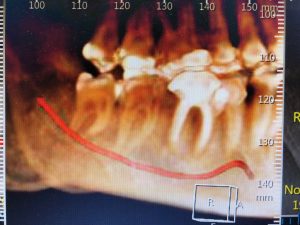

צילום שיניים פנורמי מסייע באבחון הבעיה בבסיסם של כל טיפולי השיניים קיימת קבלת החלטות המתבצעת על ידי הצוות הרפואי ועל ידי המטופלים הבאים לקבל את